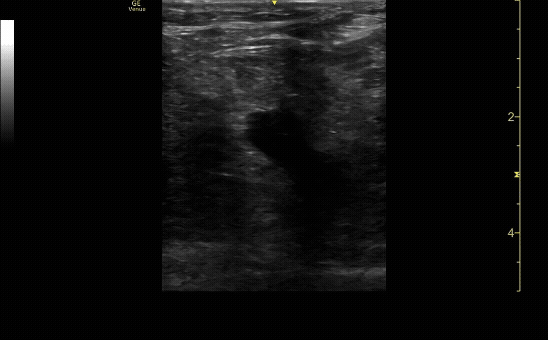

Ultrasound showing the popliteal trifurcation and compression just proximal to the popliteal vein. Be sure to show the vein before and after compression.

c/o Samson Frendo, MD